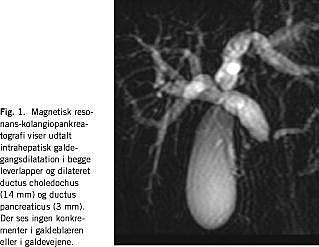

Ved indlæggelsen var alaninaminotransferase (ALAT) 146 U/l (0-35), øvrige blodprøver var normale. Efter en uge steg ALAT til 382, basisk forfataser var 1.072 U/l (250-1.000), og bilirubin var 73 μ M (< 17). Amylasen og ioniseret calcium var normale. Urinstiks var blank. En abdominal UL gav mistanke om pancreatitis. Ved magnetisk resonans-kolangiopankreatografi (MRCP) fandtes udtalt intrahepatisk galdegangsdilatation. Ductus choledocus og ductus pancreaticus var dilaterede og kunne følges til caput pancreatis, men var ikke synlige i caput, hvilket tydede på en kompression (Fig. 1 ). På de aksiale snit sås ødem af pancreas, fortrinsvis i caput og broget opladning efter kontrast, hvilket tydede på inflammation. Endoskopisk retrograd kolangiopankreatikografi viste en trådfin striktur umiddelbart inden for papillen, men ingen sten. Der blev indlagt en endoprotese i nederste del af cholodocus. Patienten havde tydelig bedring klinisk og paraklinisk efter fem uger. Patientens antistoftitre var negative for hepatitis A, Ebstein-Barr virus, cytomegalovirus og enterovirus samt Yersinia- og kuldeagglutination. Der blev ikke fundet mutationer i generne F508 og 394delTT, som i Danmark hyppigst er forbundet med cystisk fibrose. Pigen var ved efterkontrol IgG-positiv for parotitisvirus.